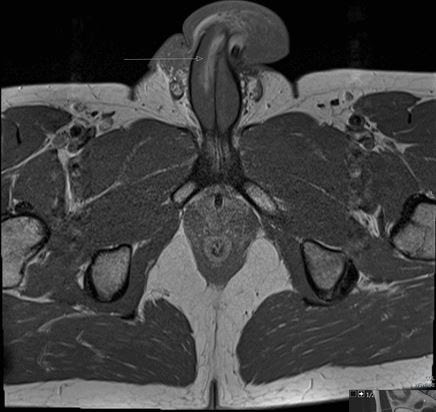

Ao analisar os resultados de uma ressonância magnética, os médicos descobriram que o pênis do homem apresentava um rasgo vertical de três centímetros de comprimento no lado direito.

Estava no meio do tronco, e não em um rasgo horizontal.